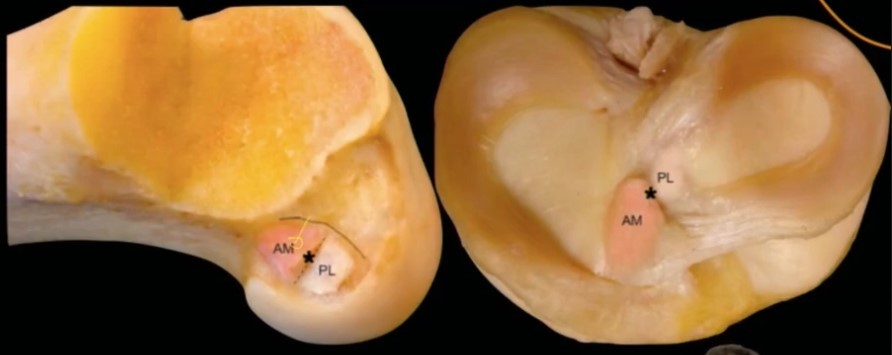

Bandas anteromedial e posterolateral AM-PL

Banda AM Tensa em flexão

Banda PL Tensa em extensão